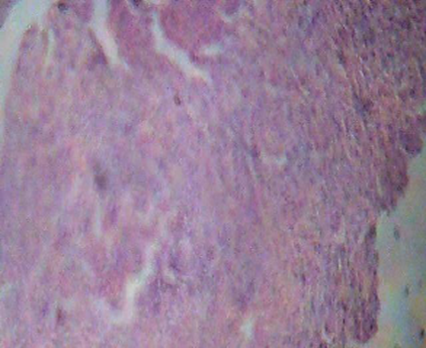

Disease Control (PCM):

The liver tissue from the disease control group (induced with Paracetamol) exhibits significant pathological alterations. There is evidence of extensive necrosis, inflammation & congestion. Hepatocytes appear degenerated and the normal liver architecture is disrupted, indicating severe liver damage and dysfunction.

Figure 1: Normal Control                             Figure 2: Disease Control